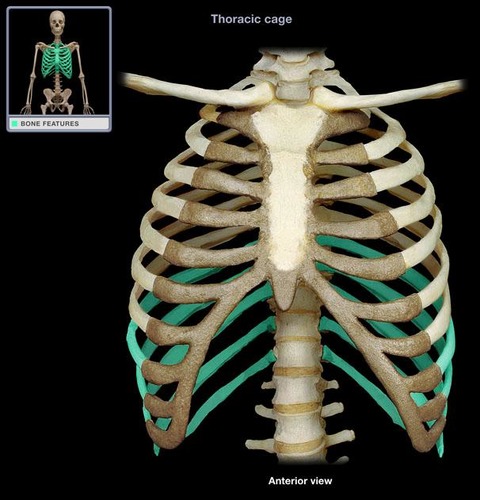

True ribs

7 pairs

False ribs

5 pairs

vertebrochondral ribs

floating ribs

costal cartilage